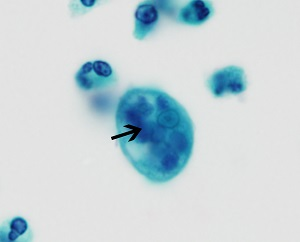

E.histolytica cyst

four nuclei and a chromatoid body with blunt ends